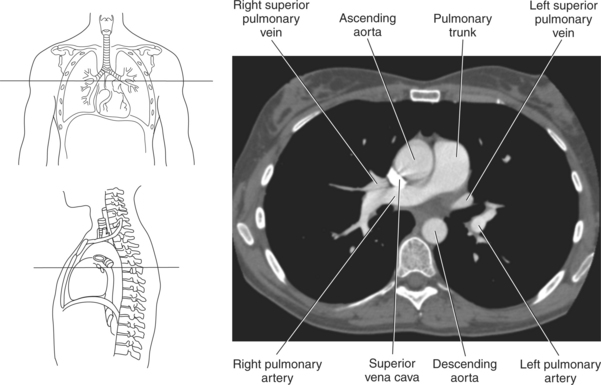

Blood travels to and from the heart through the great vessels, which include the aorta, pulmonary arteries and veins, and superior and inferior venae cavae (Figures 6.54 and 6.55). The aorta is the largest artery of the body and can be divided into the ascending aorta, aortic arch, and descending aorta. The ascending aorta begins at the base of the left ventricle at the level of the sternal angle, then curves superiorly and posteriorly as the aortic arch over the root of the left lung. The top of the aortic arch is approximately at T3 (Figures 6.56 and 6.57). The arch continues as the descending aorta posterior to the left bronchus and pulmonary trunk, on the left side of the vertebral body of T4 (Figures 6.58 and 6.59). The descending aorta passes slightly anterior and to the left of the vertebral column as it descends through the thoracic and abdominal cavities (Figure 6.60). While in the thoracic cavity, the descending aorta is commonly called the thoracic aorta, and while in the abdominal cavity, it is called the abdominal aorta. The pulmonary trunk is the origin of the right and left pulmonary arteries and lies entirely within the pericardial sac. It arises from the right ventricle and ascends in front of the ascending aorta, courses posteriorly and to the left, where it bifurcates at the level of the sternal angle (T4) into the right and left pulmonary arteries (Figures 6.61 through 6.63). The pulmonary trunk is attached to the aortic arch by a fibrous cord called the ligamentum arteriosum, the remnant of an important fetal blood vessel (ductus arteriosus) that links the pulmonary and systemic circuits during fetal development (Figures 6.54 and 6.61). The right pulmonary artery courses laterally, posterior to the ascending aorta and superior vena cava, and anterior to the esophagus and right mainstem bronchus, to the hilum of the right lung. At the root of the right lung, the right pulmonary artery divides into two branches, with the lower branch supplying the middle and inferior lobes and the upper branch supplying the superior lobe (Figures 6.61 through 6.64). The left pulmonary artery, shorter and smaller than the right, is also the most superior of the pulmonary vessels. It travels horizontally, arching over the left mainstem bronchus, and enters the hilum of the left lung just superior to the left mainstem bronchus (Figures 6.61 through 6.64). Within the lungs, each pulmonary artery descends posterolateral to the main bronchus and divides into lobar and segmental arteries, continuing to branch out and to follow along with the smallest divisions of the bronchial tree (Figures 6.61 and 6.64). Located inferior to the pulmonary arteries are the four pulmonary veins, two each (superior and inferior) extending from each lung to enter the left atrium (Figures 6.54, 6.55, 6.61, and 6.64 through 6.68). They commence in a capillary network along the walls of the alveoli, where they are continuous with the capillaries of the pulmonary arteries. The venous capillaries merge to form small vessels that unite successively to eventually form a single trunk for each lobe: three for the right and two for the left lung. Frequently the trunk from the middle lobe of the right lung unites with the trunk from the upper lobe, forming just two trunks on the right side prior to entering the left atrium. The right superior pulmonary vein collects blood from the upper lobe segments of the right lung and passes anterior and inferior to the right pulmonary artery, behind the superior vena cava. The right inferior pulmonary vein receives blood from the right lower lobes of the lung and crosses behind the right atrium to the left atrium (Figures 6.61 and 6.69 through 6.71). The left superior pulmonary vein receives blood from the left upper lobe of the left lung and courses anterior and inferior to the left main bronchus as it enters the left atrium. The left inferior pulmonary vein drains the inferior lobe of the left lung and passes toward the left atrium anterior to the bronchi (Figures 6.61 and 6.72 through 6.74). The pulmonary veins course more horizontally than the pulmonary arteries and are ultimately oriented toward the left atrium. At the root of the lungs, the pulmonary veins are anterior to the pulmonary arteries, which are anterior to the bronchus. While within the lungs, the branches of the pulmonary arteries are anterior to the bronchi, which are anterior to the pulmonary veins. The superior and inferior venae cavae are the largest veins of the body. The superior vena cava is formed by the junction of the brachiocephalic veins, posterior to the right first costal cartilage, and carries blood from the thorax, upper limbs, head, and neck (Figure 6.24). As it travels inferiorly, it is located posterior and lateral to the ascending aorta before entering the upper portion of the right atrium (Figures 6.54 through 6.59). The inferior vena cava is formed by the junction of the common iliac veins in the pelvis and ascends the abdomen to the right of the abdominal aorta and anterior to the vertebral column. It passes through the caval hiatus of the diaphragm and almost immediately enters the inferior portion of the right atrium (Figures 6.75 and 6.76).